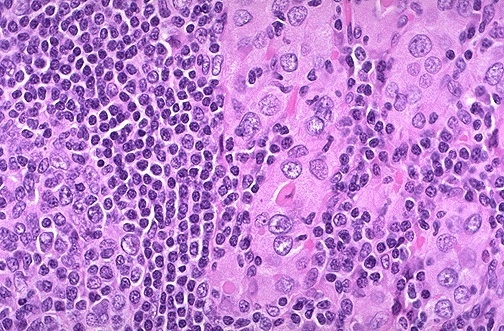

This high power microscopic view of the thyroid with Hashimoto’s thyroiditis demonstrates the pink Hürthle cells at the center and right. The lymphoid follicle is at the left. Hashimoto’s thyroiditis initially leads to painless enlargement of the thyroid, followed by atrophy years later.